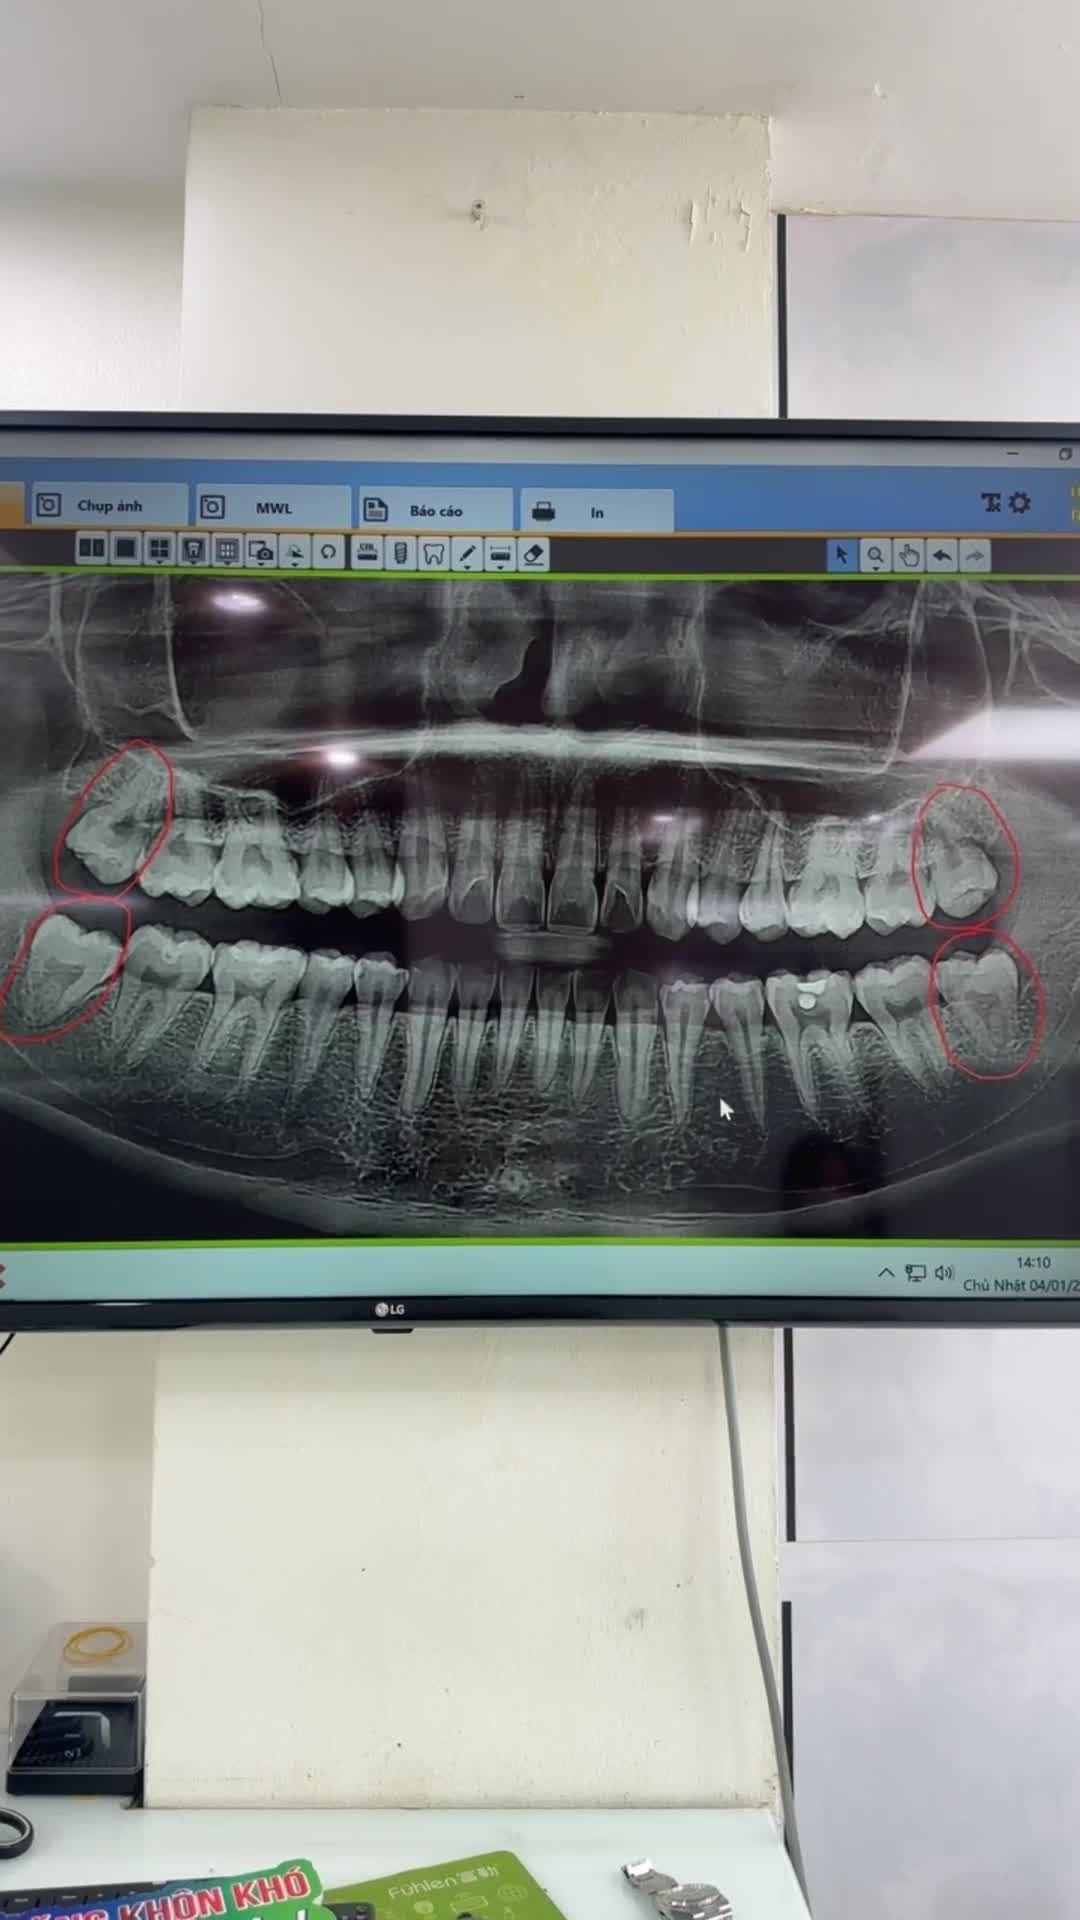

Ca nhổ răng khôn số 28; 38 lệch má cho khách hàng bạn khách hàng đang thực hiện chỉnh nha

Răng khôn tuy nhỏ nhưng ảnh hưởng tới sinh hoạt và chất lượng cuộc sống của chúng ta không hề nhỏ chút nào. Bản chất của răng khôn trên hàm là răng thừa, không có chức năng ăn nhai, đặc biệt trong trường hợp chúng mọc lệch, bị sâu, lợi trùm, viêm nhiễm,...đều được các bác sĩ khuyên nên xử lý sớm để không ảnh hưởng đến các răng kế bên, đảm bảo sức khỏe toàn diện cho hàm răng